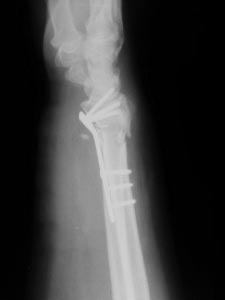

Перелом в "типичном месте" , Вопрос о фиксации шиловидного отростка

локтевой кости...

Оскольчатый перелом дистального метаэпифиза лучевой кости со смещением

отломков. Вопрос по поводу фиксации шиловидного отростка локтевой кости

Хотелось бы узнать мнения и аргументы. Надо ли фиксировать вообще?, если

да, то чем? и почему? Надеюсь на помощь коллег.